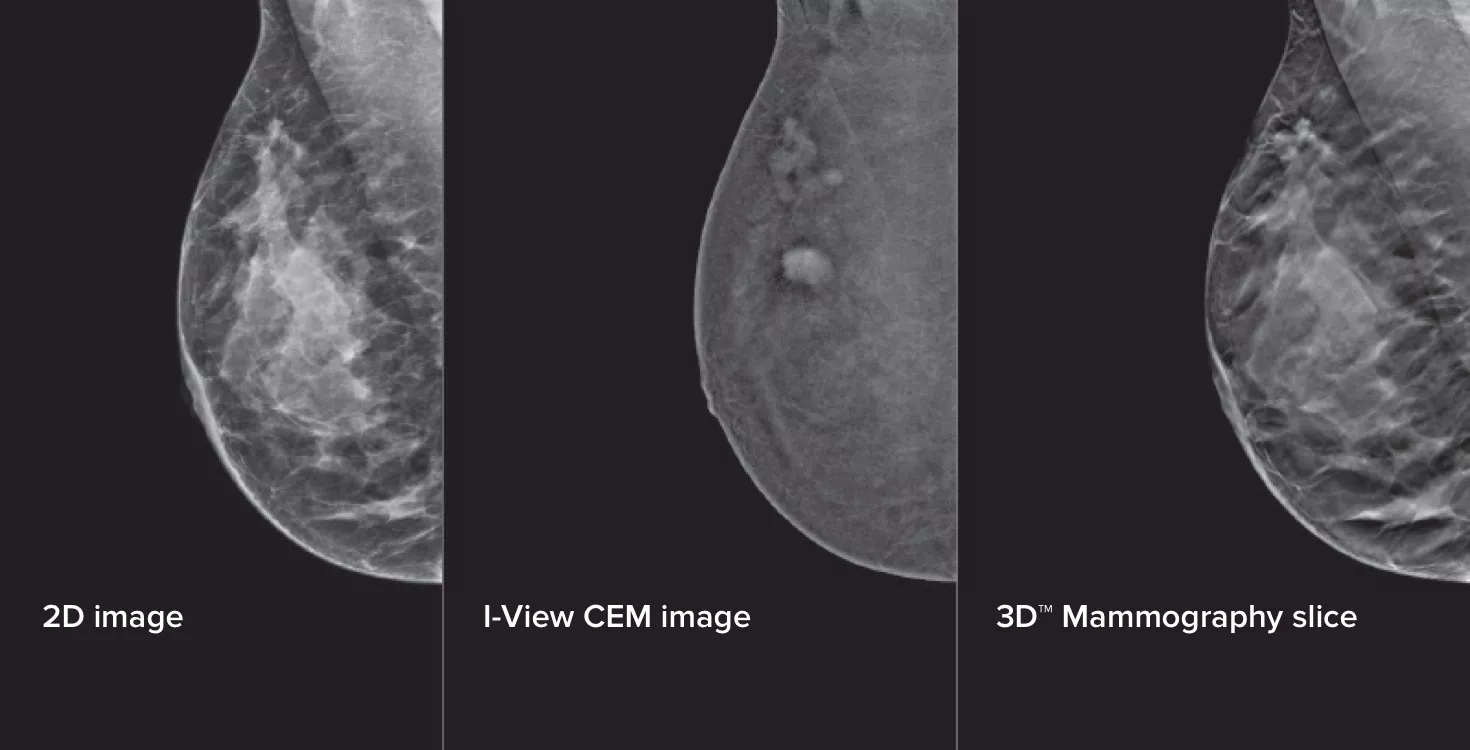

Kontrastförstärkt mammografi (CEM) är avbildning av bröst med hjälp av ett joderat kontrastmedel för att visa områden med ökad blodtillförsel i bröstet, vilket kan bidra till att förstärka bilden av misstänkta lesioner. I-View-programvaran kan kombinera kraften av CEM med 2D- och tomosyntesbilder, allt under en kompression. Detta ger anatomisk och funktionell avbildning i en undersökning.1

Tre bilder från en kompression

Denna programvara samlar in både anatomisk och funktionell information i en enda undersökning genom att utnyttja förmågan att tillhandahålla 2D-, kontrast- och tomosyntesbilder med bara en kompression.1